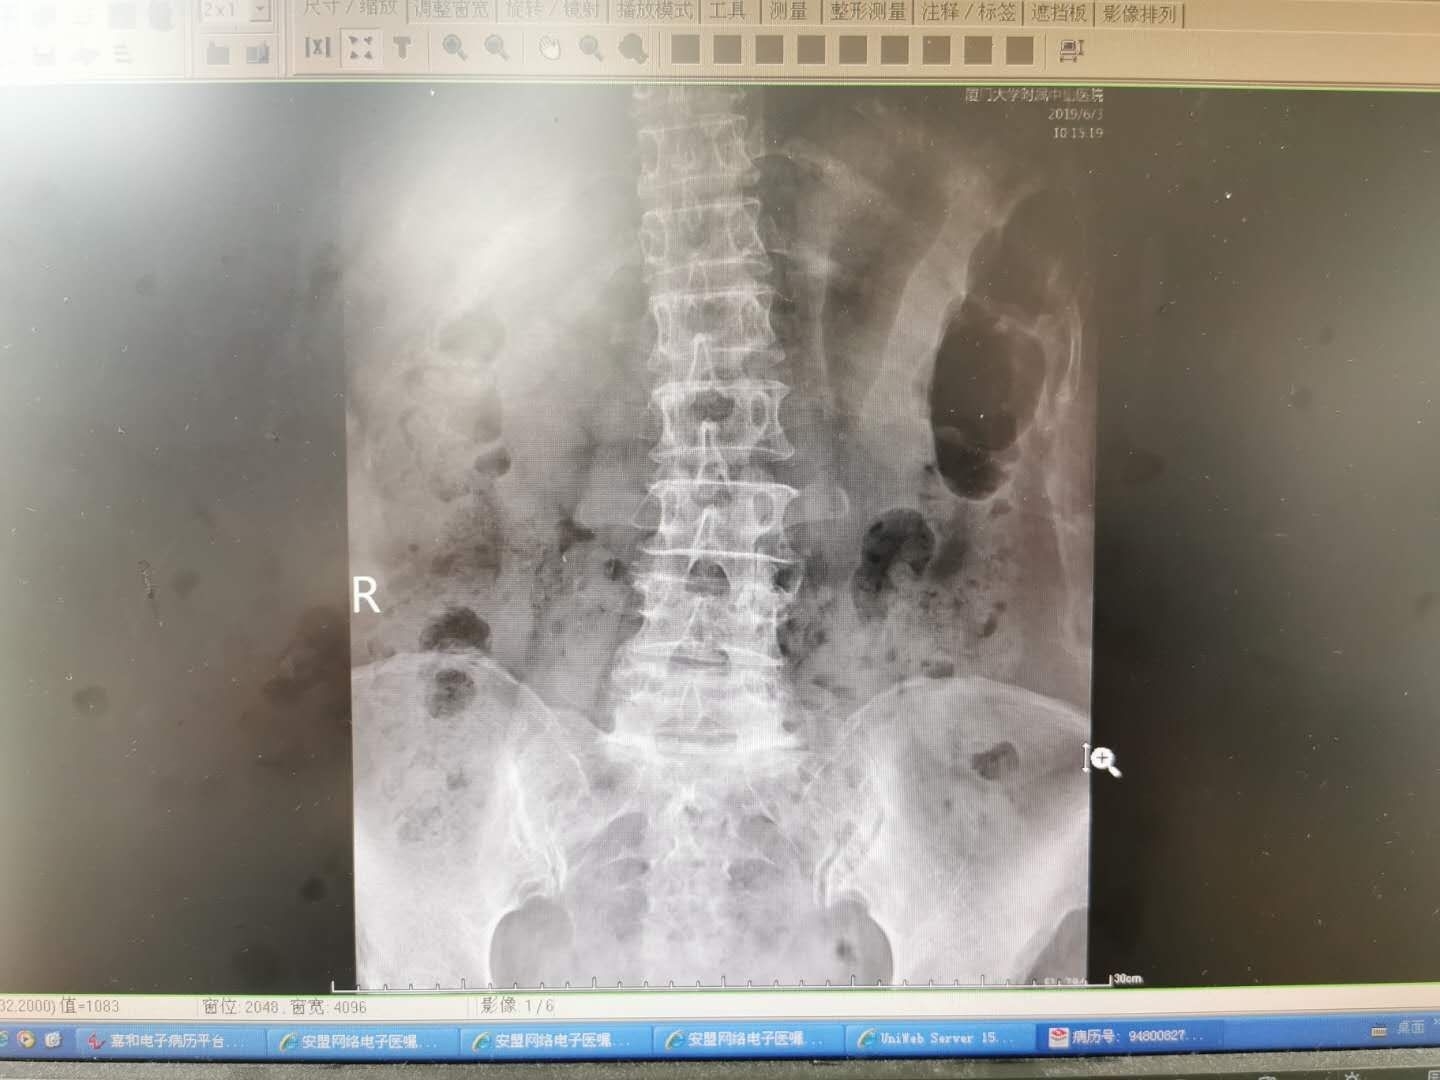

74岁,老年女性,反复腰痛十余年。近半年腰痛症状突然加重,同时伴有明显的左下肢放射痛,痛感十分剧烈,行走时必须弯着腰,卧床休息疼痛也不能缓解,夜不能寐。左侧直腿抬高试验10度。在外院尝试的口服药物,针灸,理疗,按摩均无效。在我院查X线提示腰椎退行性侧弯。CT提示腰4/5椎间盘突出。腰5/骶1椎间盘脱出。